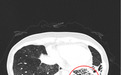

当她被推进北大深圳医院急诊大厅时,急诊科立即启动急危重症孕产妇绿色通道,值班急诊医生快速评估,患者的血压已接近休克阈值,心率100次/分,血氧饱和度95%,CT显示左下肺、左上肺舌段、右中肺支气管扩张。